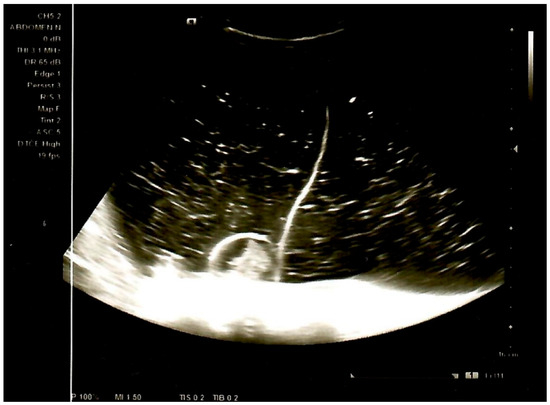

Background: Collision tumors, especially in the ovary, are a rare phenomenon where two distinct types of tumors develop adjacent to each other within the same organ but remain separate histologically. We present a case of the first collision ovarian tumor in a [...] Read more.

Background: Collision tumors, especially in the ovary, are a rare phenomenon where two distinct types of tumors develop adjacent to each other within the same organ but remain separate histologically. We present a case of the first collision ovarian tumor in a 14-year-old girl consisting of a combined tumor and a mature teratoma. Case Report: A 14-year-old girl presented with abdominal swelling for the past three months, without other symptoms. Ultrasound (US) examination of the abdomen revealed a large cystic mass with multiple septa, filling the entire abdomen from the diaphragm to the pelvis. Magnetic resonance imaging (MRI) showed an intraperitoneal mass, inseparable from the right ovary, measuring 22 cm × 13 cm × 30 cm. Serum tumor markers were within normal limits. The tumor mass was completely extirpated along with the fallopian tube. Histological and immunohistochemical analysis determined that it was a mucinous cystadenocarcinoma, characterized by a transition pattern from benign and borderline components to an adenocarcinoma component with a smaller mature teratoma. Six-month follow-up revealed no recurrence or postoperative complications. Conclusions: As the first documented case, this case provides valuable insights into pediatric ovarian neoplasms, guiding future diagnostic and therapeutic approaches. Full article

Show Figures

Figure 1